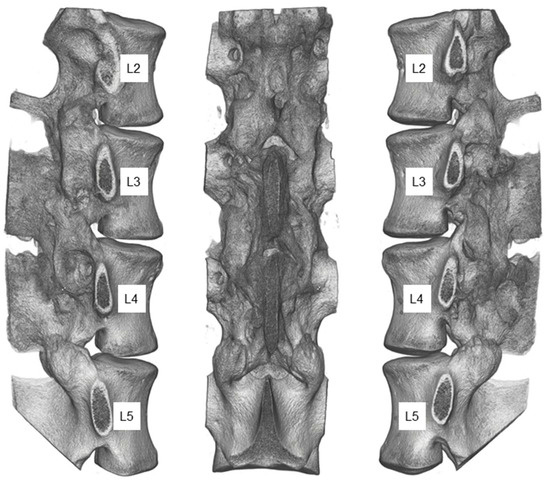

2.2. Animal Study

2.3. Postmortem Evaluation